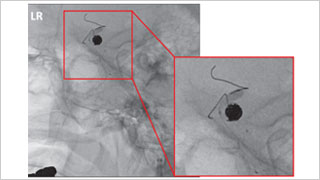

Trinias在脑动脉瘤弹簧圈栓塞术中的性能

德洲会 名古屋德洲会综合医院 脑神经外科

天野 贵之